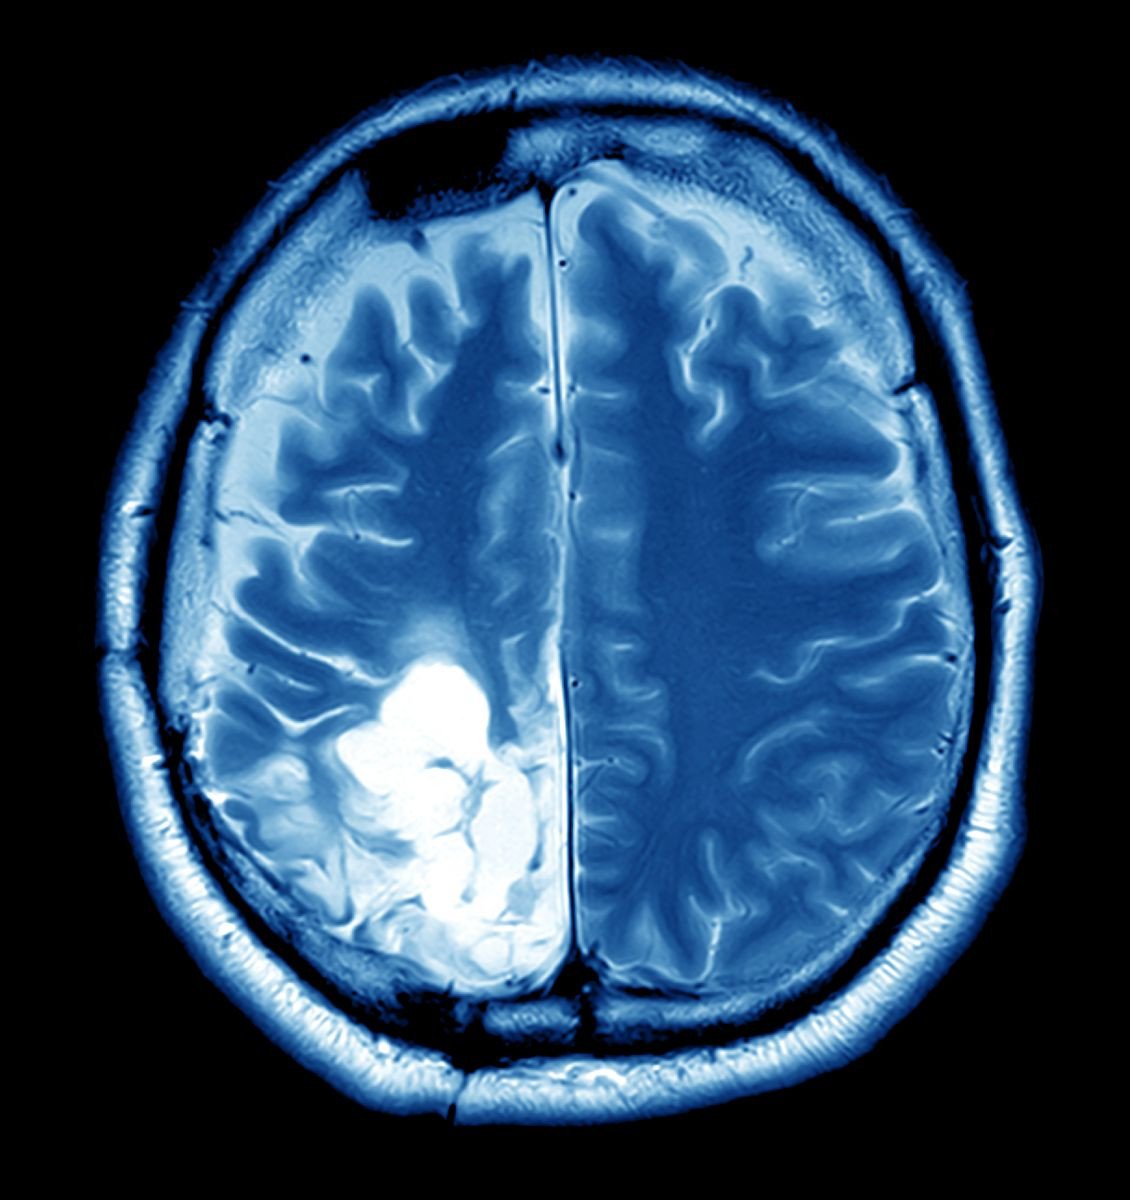

In the bustling city of Mumbai, where the vibrancy of life is palpable, lived a spirited woman named Lakshmi. A school teacher by profession, she was adored by her students for her infectious enthusiasm and unwavering dedication. However, her life took an unexpected turn when she started experiencing frequent headaches and dizzy spells, symptoms that she initially dismissed as stress-related. Little did she know, a silent adversary was growing within her— a brain tumor.

Lakshmi's world was turned upside down when she received her diagnosis. The news was not just a medical revelation but an emotional upheaval, casting a shadow over her dreams and aspirations. The fear of the unknown loomed large, and the thought of surgery was daunting. However, in her search for hope and healing, Lakshmi discovered a path that promised not just medical intervention but a comprehensive approach to her recovery.

One of the major challenges faced by individuals like Lakshmi is the overwhelming fear and uncertainty that accompanies a brain tumor diagnosis. It is not just the physical symptoms that are debilitating, but the emotional turmoil that can be equally paralyzing. The fear of losing cognitive abilities, the anxiety about surgical outcomes, and the impact on personal and professional life can be overwhelming. But this is where specialized brain tumor surgery services step in, offering a beacon of hope.

Lakshmi embarked on her journey at a renowned neurotrauma care center, known for its cutting-edge technology and compassionate care. The center's approach was holistic, addressing not only the tumor but also the emotional and psychological needs of their patients. The team of specialists, including neurosurgeons, psychologists, and rehabilitation experts, worked in unison to craft a personalized treatment plan for Lakshmi.

The surgery, though complex, was a testament to the advances in medical technology and the expertise of the surgical team. But what truly made a difference in Lakshmi's journey was the post-operative care. The center recognized that healing is multifaceted, involving physical recovery, emotional resilience, and mental well-being. Lakshmi was not just another case; she was a person with dreams, aspirations, and a life to live beyond her diagnosis.